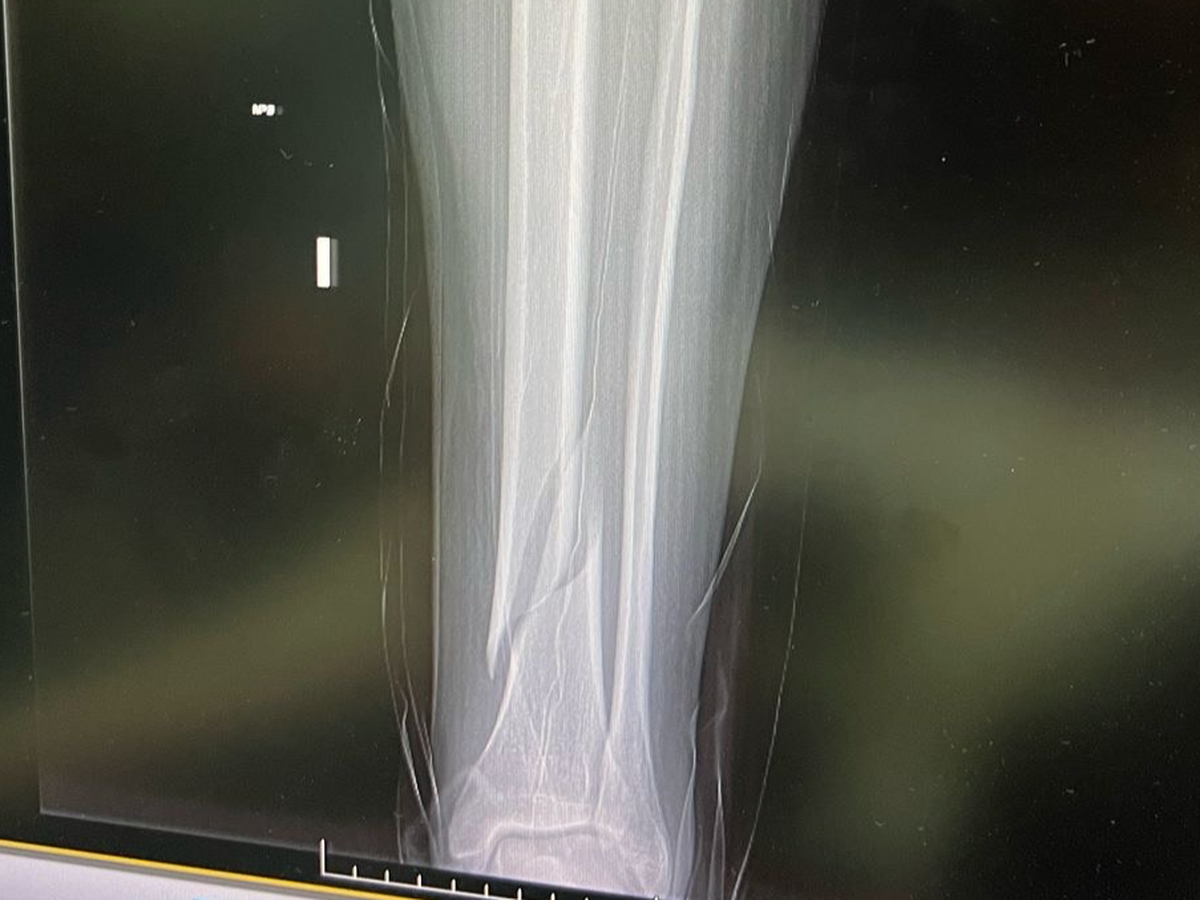

In a bit of a freak accident Stacy Pettigrew managed to fracture both her tibia and fibia in three places, two of which fractures will need surgery to resolve, after falling down two stairs. Anyone who knows how physically fit Stacy is will know how hard it is to imagine her injuring herself by doing something so innocuous but here we are.

Unfortunately in the hospital she is in, they have advised she is unlikely to receive the surgery she needs for a up to a month. This means a month of the fracture not being fixed and Stacy being in severe pain and unable to move her leg. Although her leg is immobilised in a cast, an open fracture in a leg for a month carries a various health risks if left untreated, as does spending a month in a hospital bed.